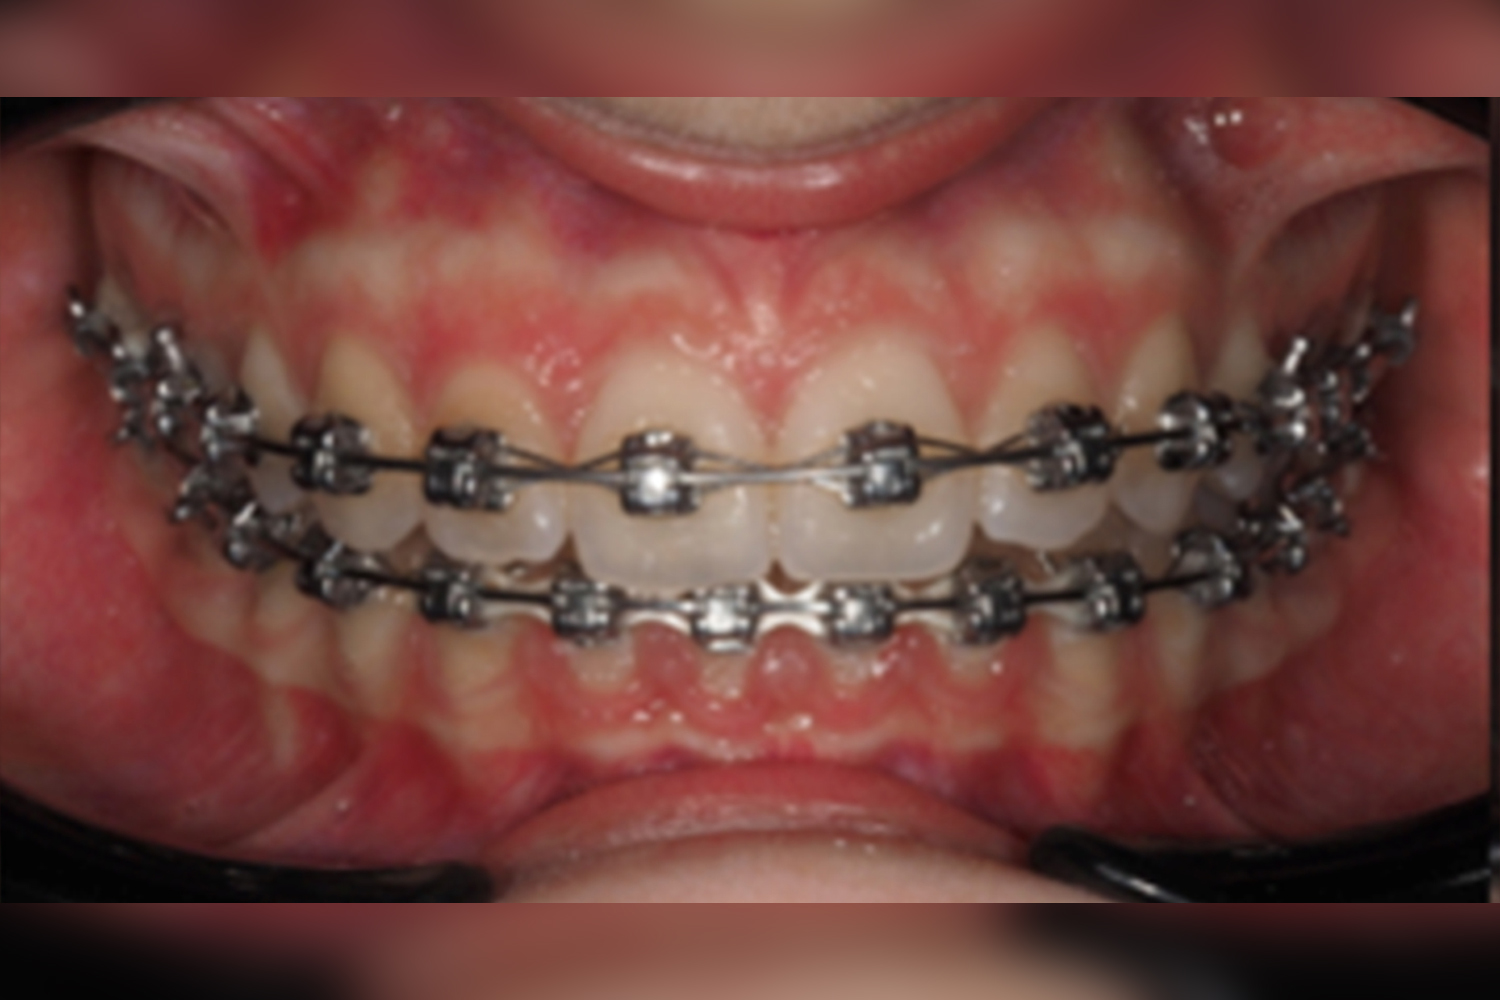

This case report shows the successful use of torque teaming with Damon Ultima brackets in a class II patient.

In view of the clinical and cephalometric data, nowadays, Dr. Iraola would rather use procline bracketsin lower incisions as well as in the UL2 for better vertical control of deep bite.

In spite of the mesial movement of the lower arch for class II correction during the treatment, the lowerincisors did not show any secondary proinclination as it was supposed. Therefore, additional overdrivewire would be also an option for extra torque expression.

Final records – March 2023